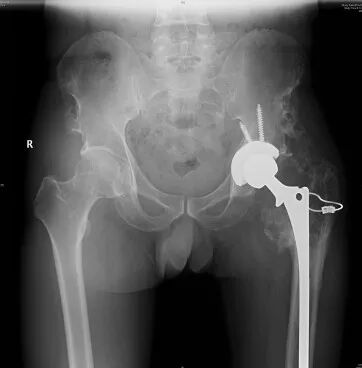

患者魯阿姨,64歲,10歲開始無明顯誘因引發(fā)雙側(cè)髖部疼痛,活動后疼痛加重,雙髖關(guān)節(jié)活動受限。近幾年以來右側(cè)髖部疼痛加重,右側(cè)下肢無力加重,行走跛行。

家人帶著魯阿姨找到了省級知名骨科專家、邦爾骨科集團首席專家、嘉興邦爾骨科醫(yī)院院長趙凱教授,診斷為“雙側(cè)先天性髖關(guān)節(jié)脫位+雙側(cè)股骨頭無菌性壞死”,并進行了“右側(cè)先天性髖關(guān)節(jié)脫位髖臼重建術(shù)+全髖關(guān)節(jié)置換術(shù)+截骨矯形術(shù)”,術(shù)后患者恢復(fù)良好,能夠正常行走。